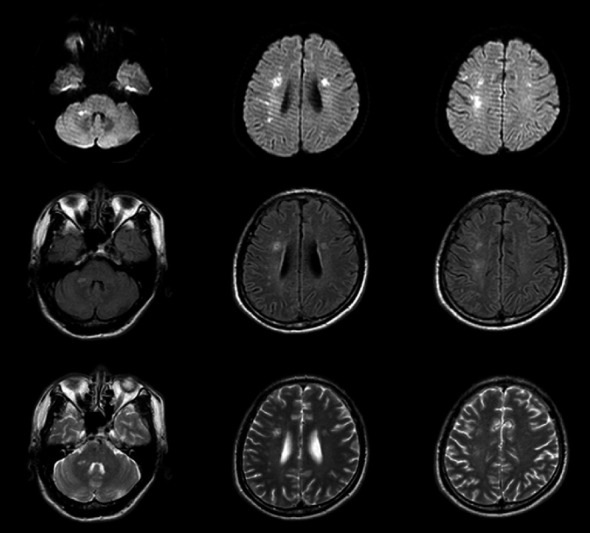

In order to discuss the clinical and MRI features, diagnosis, and prevention of myelin oligodendrocyte glycoprotein antibody-associated disease (MOGAD), we reported an adult case of MOG antibody-related disease misdiagnosed as cerebral infarction. This patient's first clinical symptom was limb weakness, that different from previous reports of MOG antibody-related diseases, such as brainstem encephalitis, neuromyelitis optical, and transverse myelitis. The main treatment plan is high-dose corticosteroid therapy combined with immunoglobulin therapy. This case indicated that some MOGAD patients lack of specificity in the clinical manifestations and imaging perhaps would be misdiagnosed as cerebral infarction, encephalitis, immune peripheral neuropathy, MS, NMOSD, and other diseases. For patients with atypical clinical manifestations or imaging, it is especially important to take antibody detection as early as possible to make correct diagnosis and active treatment in time to avoid disability.

Abstract Image